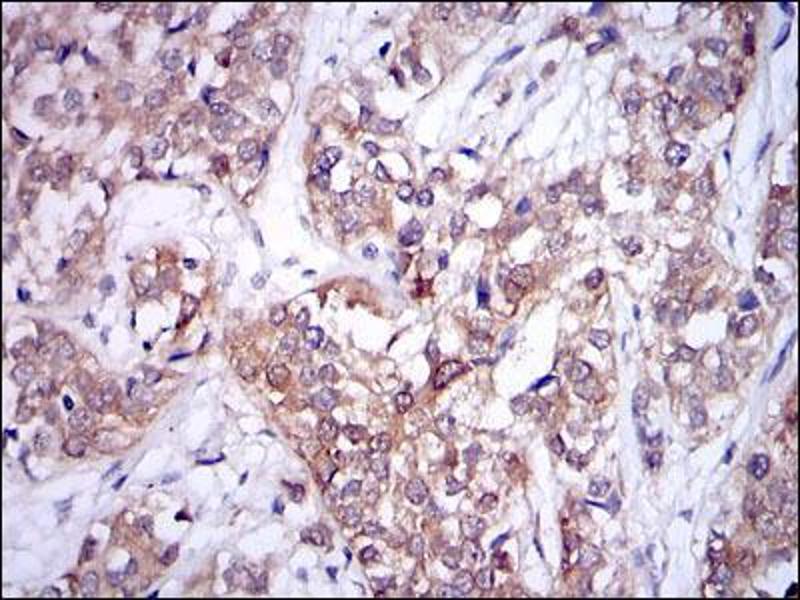

L'immunohistochimie (IHC) désigne le processus de détection des antigènes dans les cellules d'une coupe de tissu en exploitant le principe de liaison spécifique des anticorps aux antigènes des tissus biologiques. Elle est largement utilisée dans le diagnostic des cellules anormales comme celles que l'on trouve dans les tumeurs cancéreuses et dans la recherche fondamentale pour comprendre la distribution et la localisation des biomarqueurs et des protéines exprimées de manière différentielle dans différentes parties d'un tissu biologique. Visualiser une interaction anticorps-antigène peut être accompli de plusieurs façons. Dans le cas le plus courant, un anticorps est conjugué à une enzyme, comme la peroxydase, qui peut catalyser une réaction produisant une couleur, ou marqué à un fluorophore.